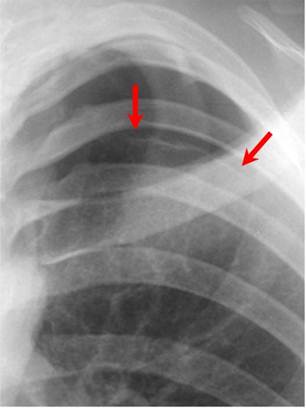

Red arrows point to thin white visceral pleural line which

is the single best sign for a pneumothorax

- Must see the visceral pleural white line

- Very thin white line that differs from a skin fold by its thickness

- Absence of lung markings distal or peripheral to the visceral pleural white line